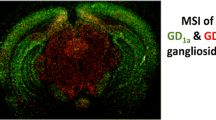

An advantage of MALDI MSI is the possibility to perform multiple measurements with different settings on the same tissue, in order to detect a broad range of biomolecules33. For instance, simultaneous and correlative MS imaging of drug and heme group has been validated as a method to visualize the lumen of the blood vessels in the brain and, thus, permeability through the BBB34. Therefore, we examined the presence of remaining blood in the same tissue slice in a simple label-free way by MALDI imaging of hemoglobin (HB). We imaged first DPPG and ICG in negative ion reflector mode and PEG36-DSPE in positive ion reflector mode with PhCCAA matrix and afterwards HB in positive ion linear mode with sDHB matrix (Fig. 5A). Prior to sDHB application and protein imaging, the tissue was washed to remove PhCCAA and the lipid background. The imaged signals of liposomal components showed lower intensity in single spectra measured on the tissue of perfused mice. But DPPG, PEG36-DSPE, ICG (weak) as well as low amounts of HB were detected even in the brains of perfused mice by MALDI MSI. To conduct in-depth computational evaluation of these MS images, we programmed an analysis tool in R for pixel-by-pixel correlation analysis of the three m/z values for DPPG, PEG36-DSPE and HB. In two brain slices from non-perfused mice, 57% and 72% of all pixels contained HB, whereas only 11% of pixels in both perfused brain slices contained HB.

Images on brains of mice that were dosed with liposomes and localization of the detected liposomes.

(A) MALDI MSI images were performed on brain slices of mice that were dosed with liposomes. Half of the mice were perfused before being sacrificed (right panels) to reduce the remaining blood in the tissue. MALDI images of DPPG and ICG were acquired in reflector negative ion mode, of PEG36-DSPE in reflector positive mode and of HB α chain in linear positive mode. DPPG, ICG and PEG36-DSPE were measured with PhCCAA MALDI matrix. HB was detected after delipidation and sDHB deposition on the same tissue region. (B) Fluorescence images performed on brain slices of mice that were dosed with liposomes. (C) HE staining of tissue slices measured with MALDI MSI. (D) Magnification of MALDI MS images of the boxed parts marked in perfused brain in (A) and HE stained brain in (C). Pixels indicated by an arrow shows the co-localisation of the liposomal components and hemoglobin at pixel X442 Y071 and the absence of HB at pixel X449 Y074.

We therefore performed computational correlation analysis on slices from perfused brains: As expected, almost all pixels that displayed signals for the two lipid markers also provided analytical evidence for the blood marker HB suggesting that liposomes were present in blood vessels of the brain. A single pixel spectrum measured at motor position X442 Y071 served as an example for this notion (Suppl. Figure 05A): Besides the signals of DPPG, ICG (A1) and PEG36-DSPE (A2), the signal of HB (A3) was also evident for this pixel. Neighboring single pixel spectra showed the same signals. Therefore, it is highly likely that the imaged structure shown in the magnification (Fig. 5B) represents a blood vessel that was not fully rinsed by perfusion. Apparently, residual liposome-containing blood remained after the perfusion procedure. In contrast, in pixel X449 Y074 near to this presumed vessel the liposomal components DPPG and PEG36-DSPE but virtually no HB was detected (Suppl. Figure 05B). The apparent absence of HB from the X449 Y074 single pixel spectra and mass spectra of surrounding pixels either indicates the entrance of liposomal components into brain tissue or the presence of liposomes in a vessel where blood had been completely removed. Overall, only three such pixels (out of about 4000) were found in brains of perfused mice. In brains of non-perfused mice, no such pixels were identified. Suppl. Figure 05 shows the single spectra for all these pixels (B–D). While the pixels identified at motor position X449 Y074 (B) and X451 Y083 (C) were located in the hippocampal formation in the brain of the first perfused mouse, the pixel X494 Y153 (D) was identified in the second perfused mouse brain in the lateral forebrain bundle.

Using MALDI MSI, we detected all liposomal compounds in livers (Fig. 2A), kidneys (Fig. 2B) and even in brains (Fig. 3) of mice dosed with liposomes. Transport of drugs and drug carriers from the circulating blood into the brain is restricted by the BBB. Conventional liposomes do not cross it40,41,42. Also PEGylated liposomes like the ones used here do not cross the intact BBB43,44. Improved drug delivery across the intact BBB can be achieved by actively transported targeted drug carriers smaller than 180 nm7,45,46. In this study, following analysis of all liposomal components, we visualized residual blood in the same tissue slice by MALDI MSI to determine localization of liposomes either in brain parenchyma or the circulating blood. Traditional histomorphology visualizes the brain’s vascular system by dye perfusion or by immunohistochemistry (IHC) of marker proteins, both of which require specific labeling reagents47,48. In contrast, MALDI MS Imaging of heme is a label-free method for vasculature imaging that has been validated by Liu et al.34. However, since the heme group is a component of various proteins49, we deemed it even more specific to image m/z values of hemoglobin (HB) chains. Murine vessels in the 100–200 μm range can be visualized by MALDI MSI using m/z 14,981 (α chain) and m/z 15,617 (β chain)50 for HB51. Nevertheless, besides lower spatial resolution compared to other imaging methods, MALDI MSI exhibits currently lower sensitivity that may be caused by ion suppression52. Therefore, we used a second approach for verification of liposome localization, namely by reducing blood signals by sacrificing-perfusing half of the experimental animals. Comparing MS images of liposomal components and HB in perfused and non-perfused brains, we found the majority of liposomal components to co-localize with HB. Only three spectra of single pixels were identified by computational analysis of brains of both perfused mice where no co-localization with HB was observed. This indicated either the entrance of liposomal components into brain parenchyma or the presence of liposomes in a blood-depleted blood vessel. Absence of any single pixel spectra containing peaks for two liposomal components but no HB in non-perfused brains strongly suggests that, in accordance with the literature, the untargeted liposomes used in this study did not pass the BBB.